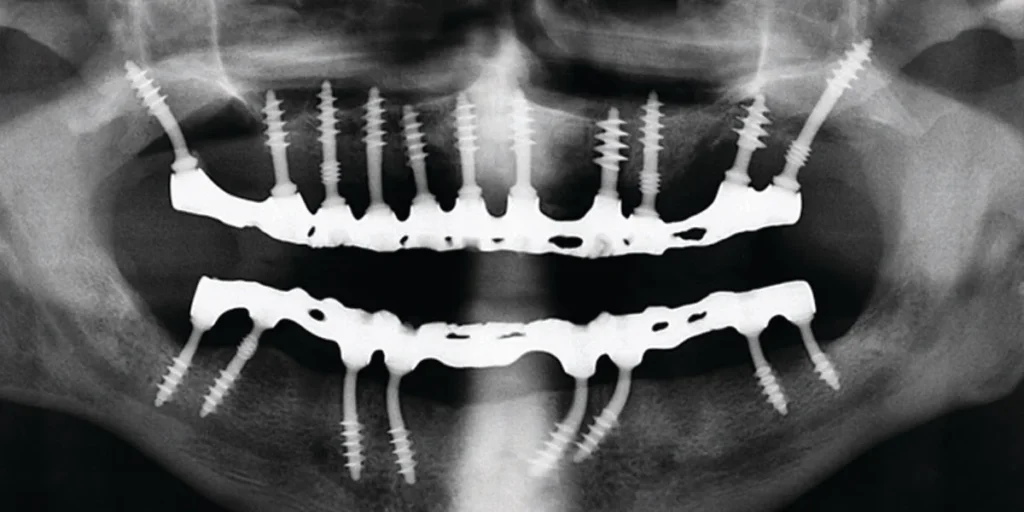

CorticoBasal® implants utilize the strong, stable cortical bone rather than the softer cancellous bone. These are single-piece implants that anchor into the basal bone, which remains unaffected even in older patients or those with periodontal disease. This allows for immediate loading – teeth are fixed within 72 hours and avoids the need for bone augmentation.